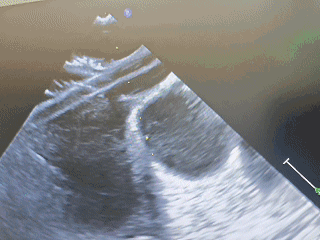

植入第一个封堵器

建立输送轨道

超声下导丝导管通过房间隔较大缺损,将导丝置于左上肺静脉,建立输送轨道

左盘展开

左盘展开与贴靠

右盘展开

固定钢缆,后撤鞘管,展开右盘

轻推鞘管,使右盘成型

锁定

确定封堵器骑跨房间隔后,锁定封堵器

锁定后牵拉

锁定后,牵拉试验

封堵器位置固定,未见明显位移及形变

成型良好

第一个封堵器形态良好